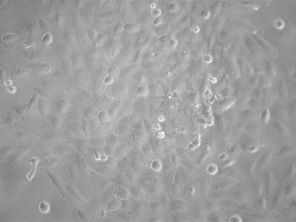

GFP Expressing Human Brain Glioblastoma Cells (LN-18)

| Artikelname: | GFP Expressing Human Brain Glioblastoma Cells (LN-18) |